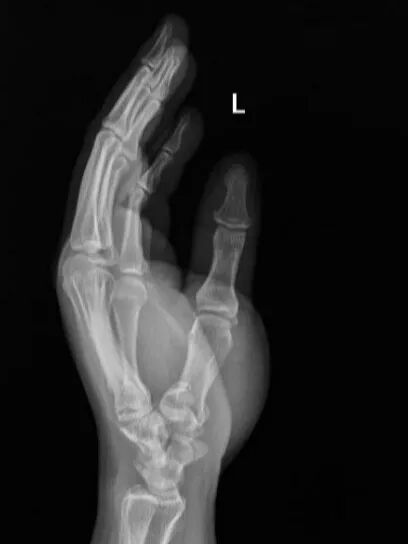

手術前左手正斜位片